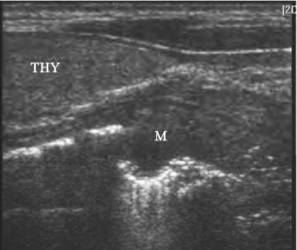

1.食管壁局限性不规则增厚或呈结节样凸入管腔,黏膜毛糙,层次结构不清(图27-4)。

图27-4 食管癌声像图

颈段食管位于甲状腺后方,壁局限性增厚THY:甲状腺;M:肿瘤